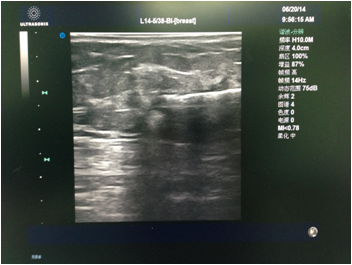

先由主刀医生行彩超检查,和患者确认及核对拟切除的目标病灶。消毒铺巾后医生在彩超引导下于表皮,手术路径及目标病灶周围注射局麻药(图1)。麻醉满意后于彩超引导下进旋切针到目标病灶下方,然后开始切除目标病灶(图2)。最后加压包扎,切除的病灶送病理检查(图3)。整个手术过程于局麻下完成,会有轻微疼痛,但一般程度不重。

图1 注射局麻药。图中黑色低回声为肿物,上方的白色条索为注射局麻药的针头。